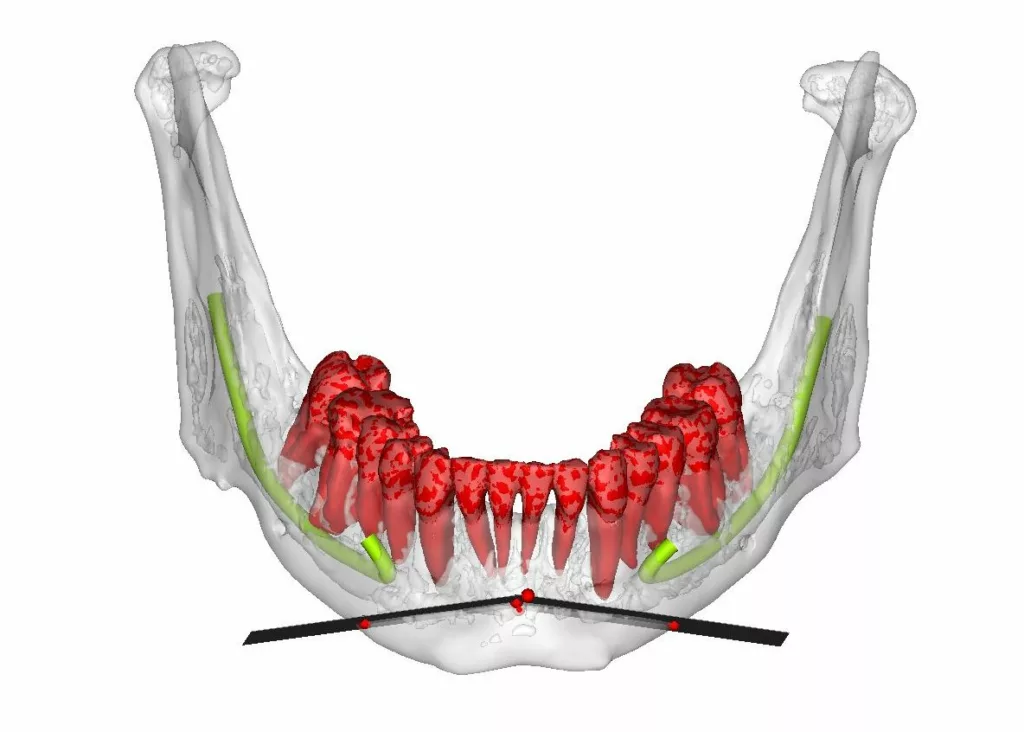

La chirurgie guidée consiste à simuler le geste opératoire au moyen de logiciels spécialisés puis à assurer le contrôle de l’exécution chirurgicale au bloc opératoire à l’aide de guides de découpe osseuse et de forage.

Des miniplaques en titane sur mesure spécifiques de l’anatomie propre à chaque patient et spécifiques des mouvements envisagés par le chirurgien permettent de stabiliser toutes les pièces anatomiques libérées par les manœuvres d’ostéotomie conformément à la simulation : plateau maxillaire, arc denté mandibulaire, branches montantes et condyles, menton .

- la chirurgie guidée requiert un bilan scanner pré-opératoire complet de l’extrémité céphalique

- une analyse céphalométrique de la situation pré-opératoire et une analyse céphalométrique de la simulation, confrontées à la situation clinique du patient et à ses aspirations sont obligatoires. Pour notre part, nous utilisons l’analyse céphalométrique de Jean Delaire qui nous semble, jusqu’à preuve du contraire, la plus performante